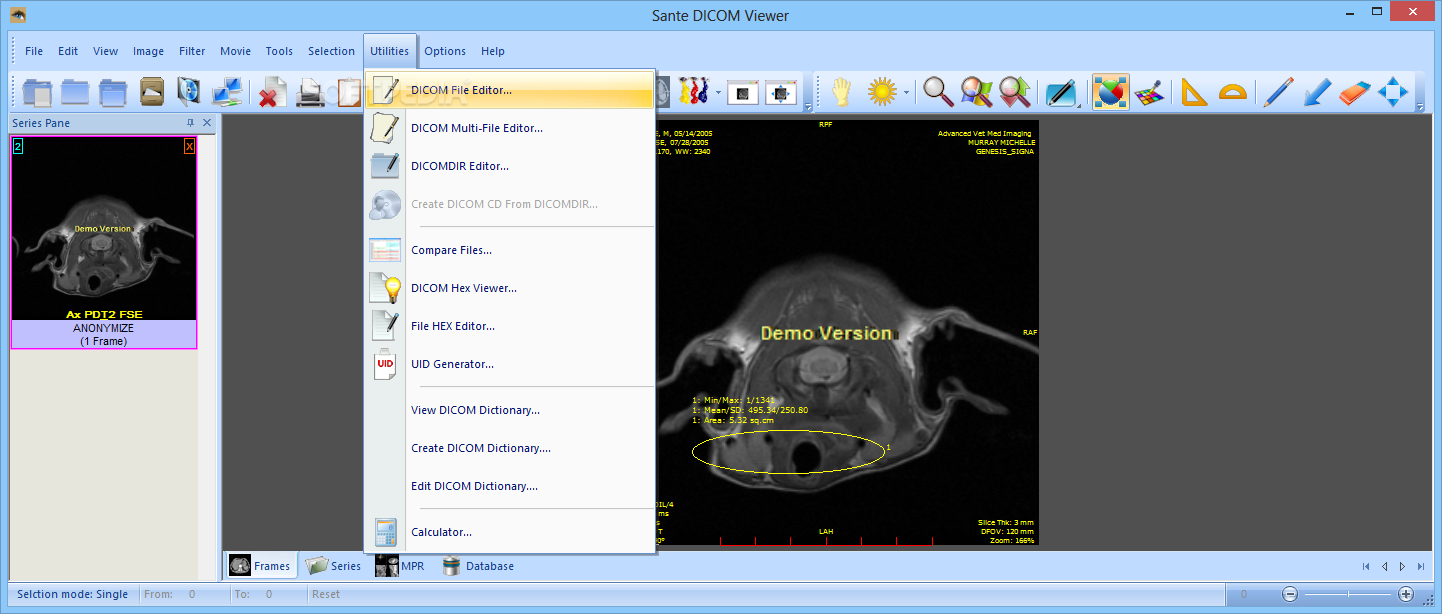

Лазерная камера сетевая для печати изображений на пленке стандарт dicom